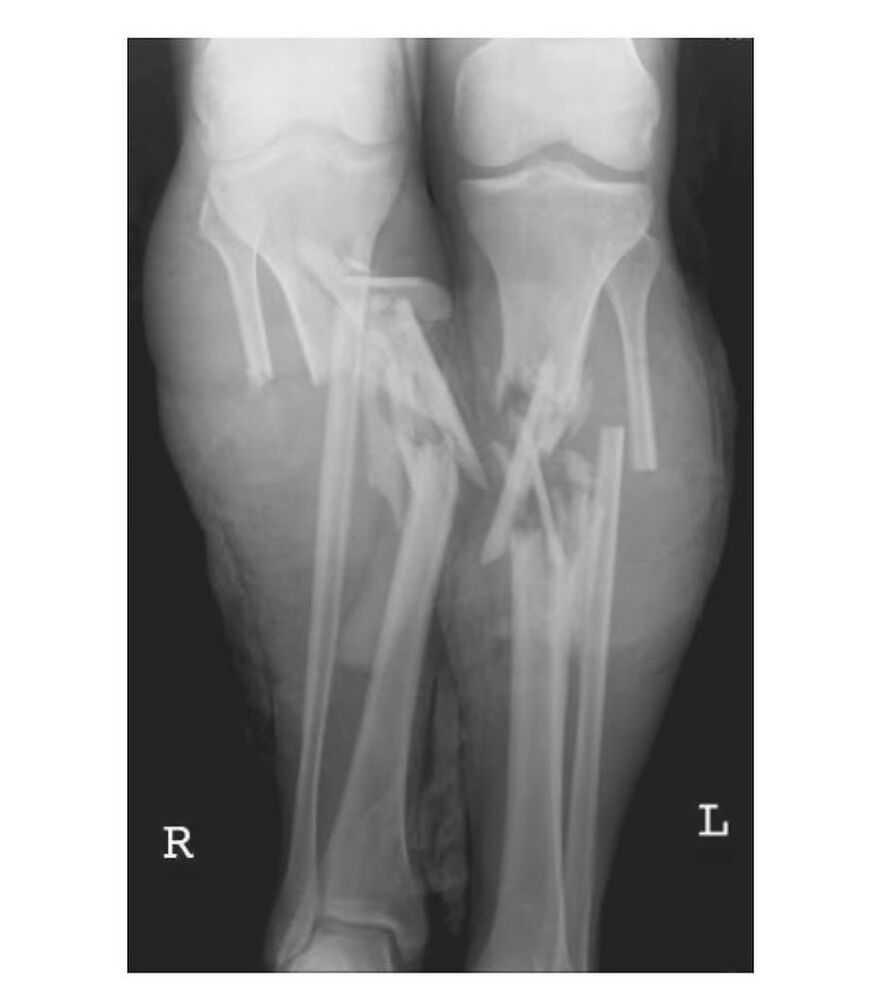

Ilizarov Apparatus

“The Ilizarov apparatus is a type of external fixator used in orthopedic surgery to lengthen bones, reshape limbs, or stabilize fractures. It's a circular frame with rods and rings that attach to the bone through wires, allowing for controlled bone lengthening and bone reconstruction.”